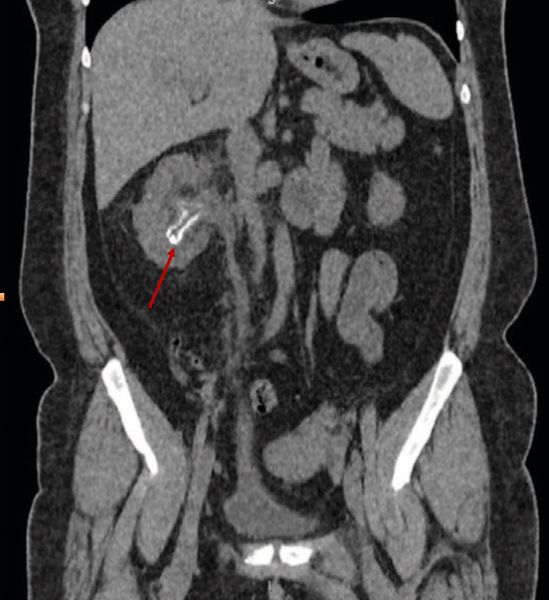

Инкрустирующий пиелит, как правило, развивается в результате воздействия Corynebacterium urealyticum. Как уже было сказано выше, эта бактерия способна расщеплять мочевину, из-за чего на стенках лоханок и чашечек формируется кристаллическая корочка, которую находят во время инструментального обследования [1].

![Инкрустирующий пиелит [1] Инкрустирующий пиелит [1]](/media/bolezny/pielit/inkrustiruyushiy-pielit-1_s.jpeg?dummy=1754648666800)

Инкрустирующий пиелит [1]